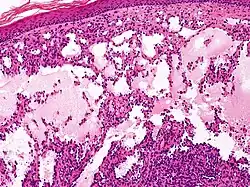

Microscopicamente, as vesículas em um linfangioma circunscrito são canais linfáticos dilatados expandindo a derme papilar. Eles podem ser associados com acantose e hiperqueratose. Há muitos canais na derme superior, muitas vezes se estendendo para o tecido subcutâneo (a camada mais profunda da derme, contendo gordura e tecido conjuntivo). Os vasos mais profundos têm grande calibre com paredes espessas que contêm musculatura lisa. O lúmen é preenchido com fluido linfático, mas muitas vezes contém glóbulos vermelhos, linfócitos, macrófagos, e neutrófilos. Os canais são revestidos com células endoteliais planas. O interstício tem muitas células linfóides e mostra evidência de fibroplasia (a formação de tecido fibroso). Nódulos (uma pequena massa de tecido ou agregação de células) em linfangiomas cavernosos são grandes canais, irregulares, na derme reticular e tecido subcutâneo que são revestidos por uma camada única de células endoteliais e uma camada incompleta de músculo liso. O estroma é constituído por tecido conjuntivo frouxo com uma grande quantidade de células inflamatórias. Estes tumores geralmente penetram a musculatura. O higroma cístico é histologicamente indistinguível de um linfangioma cavernoso. [7]

- Um linfangioma capilar é composto de vasos linfáticos de pequeno calibre, caracteristicamente localizado na epiderme.

- Linfangioma cavernoso

- Lesão única na derme que pode crescer durante a infância. Geralmente na cabeça, pescoço ou extremidades. Composto por canais linfáticos dilatados, um linfangioma cavernoso tipicamente desloca tecidos e órgãos adjacentes, podendo causar disfunção.